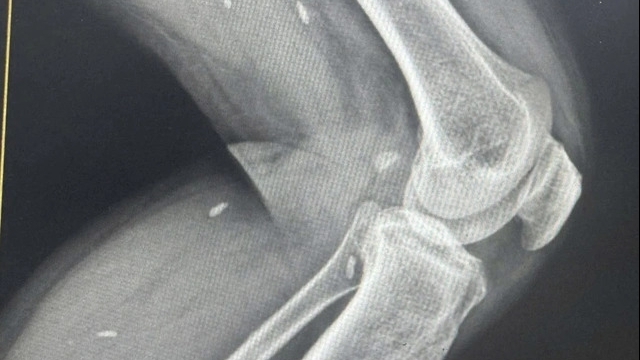

Đặc biệt, hình ảnh chụp cắt lớp cho thấy người bệnh có thận đôi hoàn toàn hai bên, tức là mỗi bên thận đều có hai hệ thống bể thận và niệu quản riêng biệt, khiến cho cấu trúc giải phẫu trở nên phức tạp hơn so với bình thường.

| Hình ảnh dựng từ phim chụp CT Scanner 3D cho thấy hệ tiết niệu của người bệnh có dị tật thận đôi hai bên (Ảnh: BVCC) |